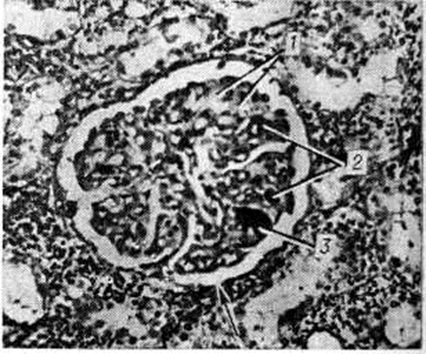

Рис. 1.

Микропрепарат почки при болезни Мошкович: стрелкой указано фибриноидное набухание и плазматическое пропитывание стенки мелкой артерии; окраска гематоксилин-эозином-, × 200.

Микроскопически во всех органах обнаруживают характерное поражение капилляров, артериол и мелких артерий, которое наиболее выражено в почках и зависит от длительности течения заболевания. При кратковременном течении (до 1 месяца) и обострении процесса преобладают фибриноидное набухание с плазматическим пропитыванием (рисунок 1) с последующим фибриноидным некрозом сосудов и окклюзией просвета эозинофильными PAS-положительными массами, дающими положительную реакцию на фибрин.